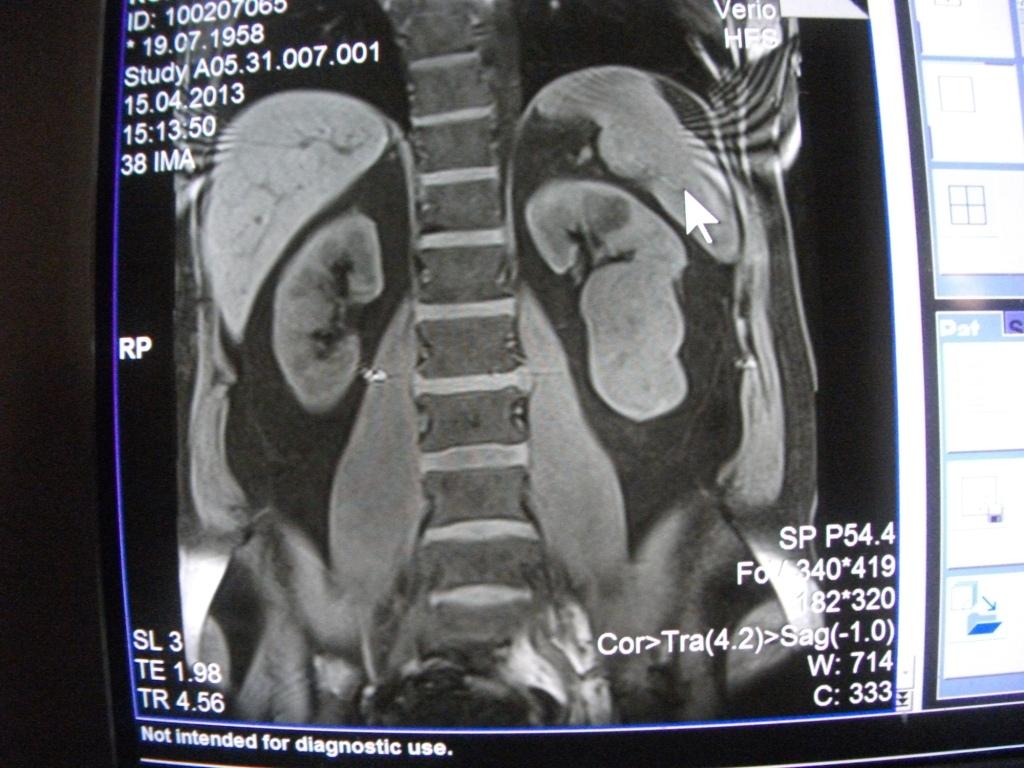

такое заключение: Левая почка: расположена обычно, увеличена, общими размерами около 13х5,5см. В области средней и нижней трети почки определяется объёмное образование неправильной формы, деформирующее наружный контур почки, распространяющиеся с чашечно-лоханочную систему. Опухоль имеет четкие неровные бугристые контуры с наличием псевдокапсулы, неоднородной структуры с признаками распада, максимальными размерами около 78,7х47х48мм

Вопрос такой: можно ли обойтись без удаления почки, удалив только опухоль.

Технически можно. Но практически - лучше нефрэктомия.